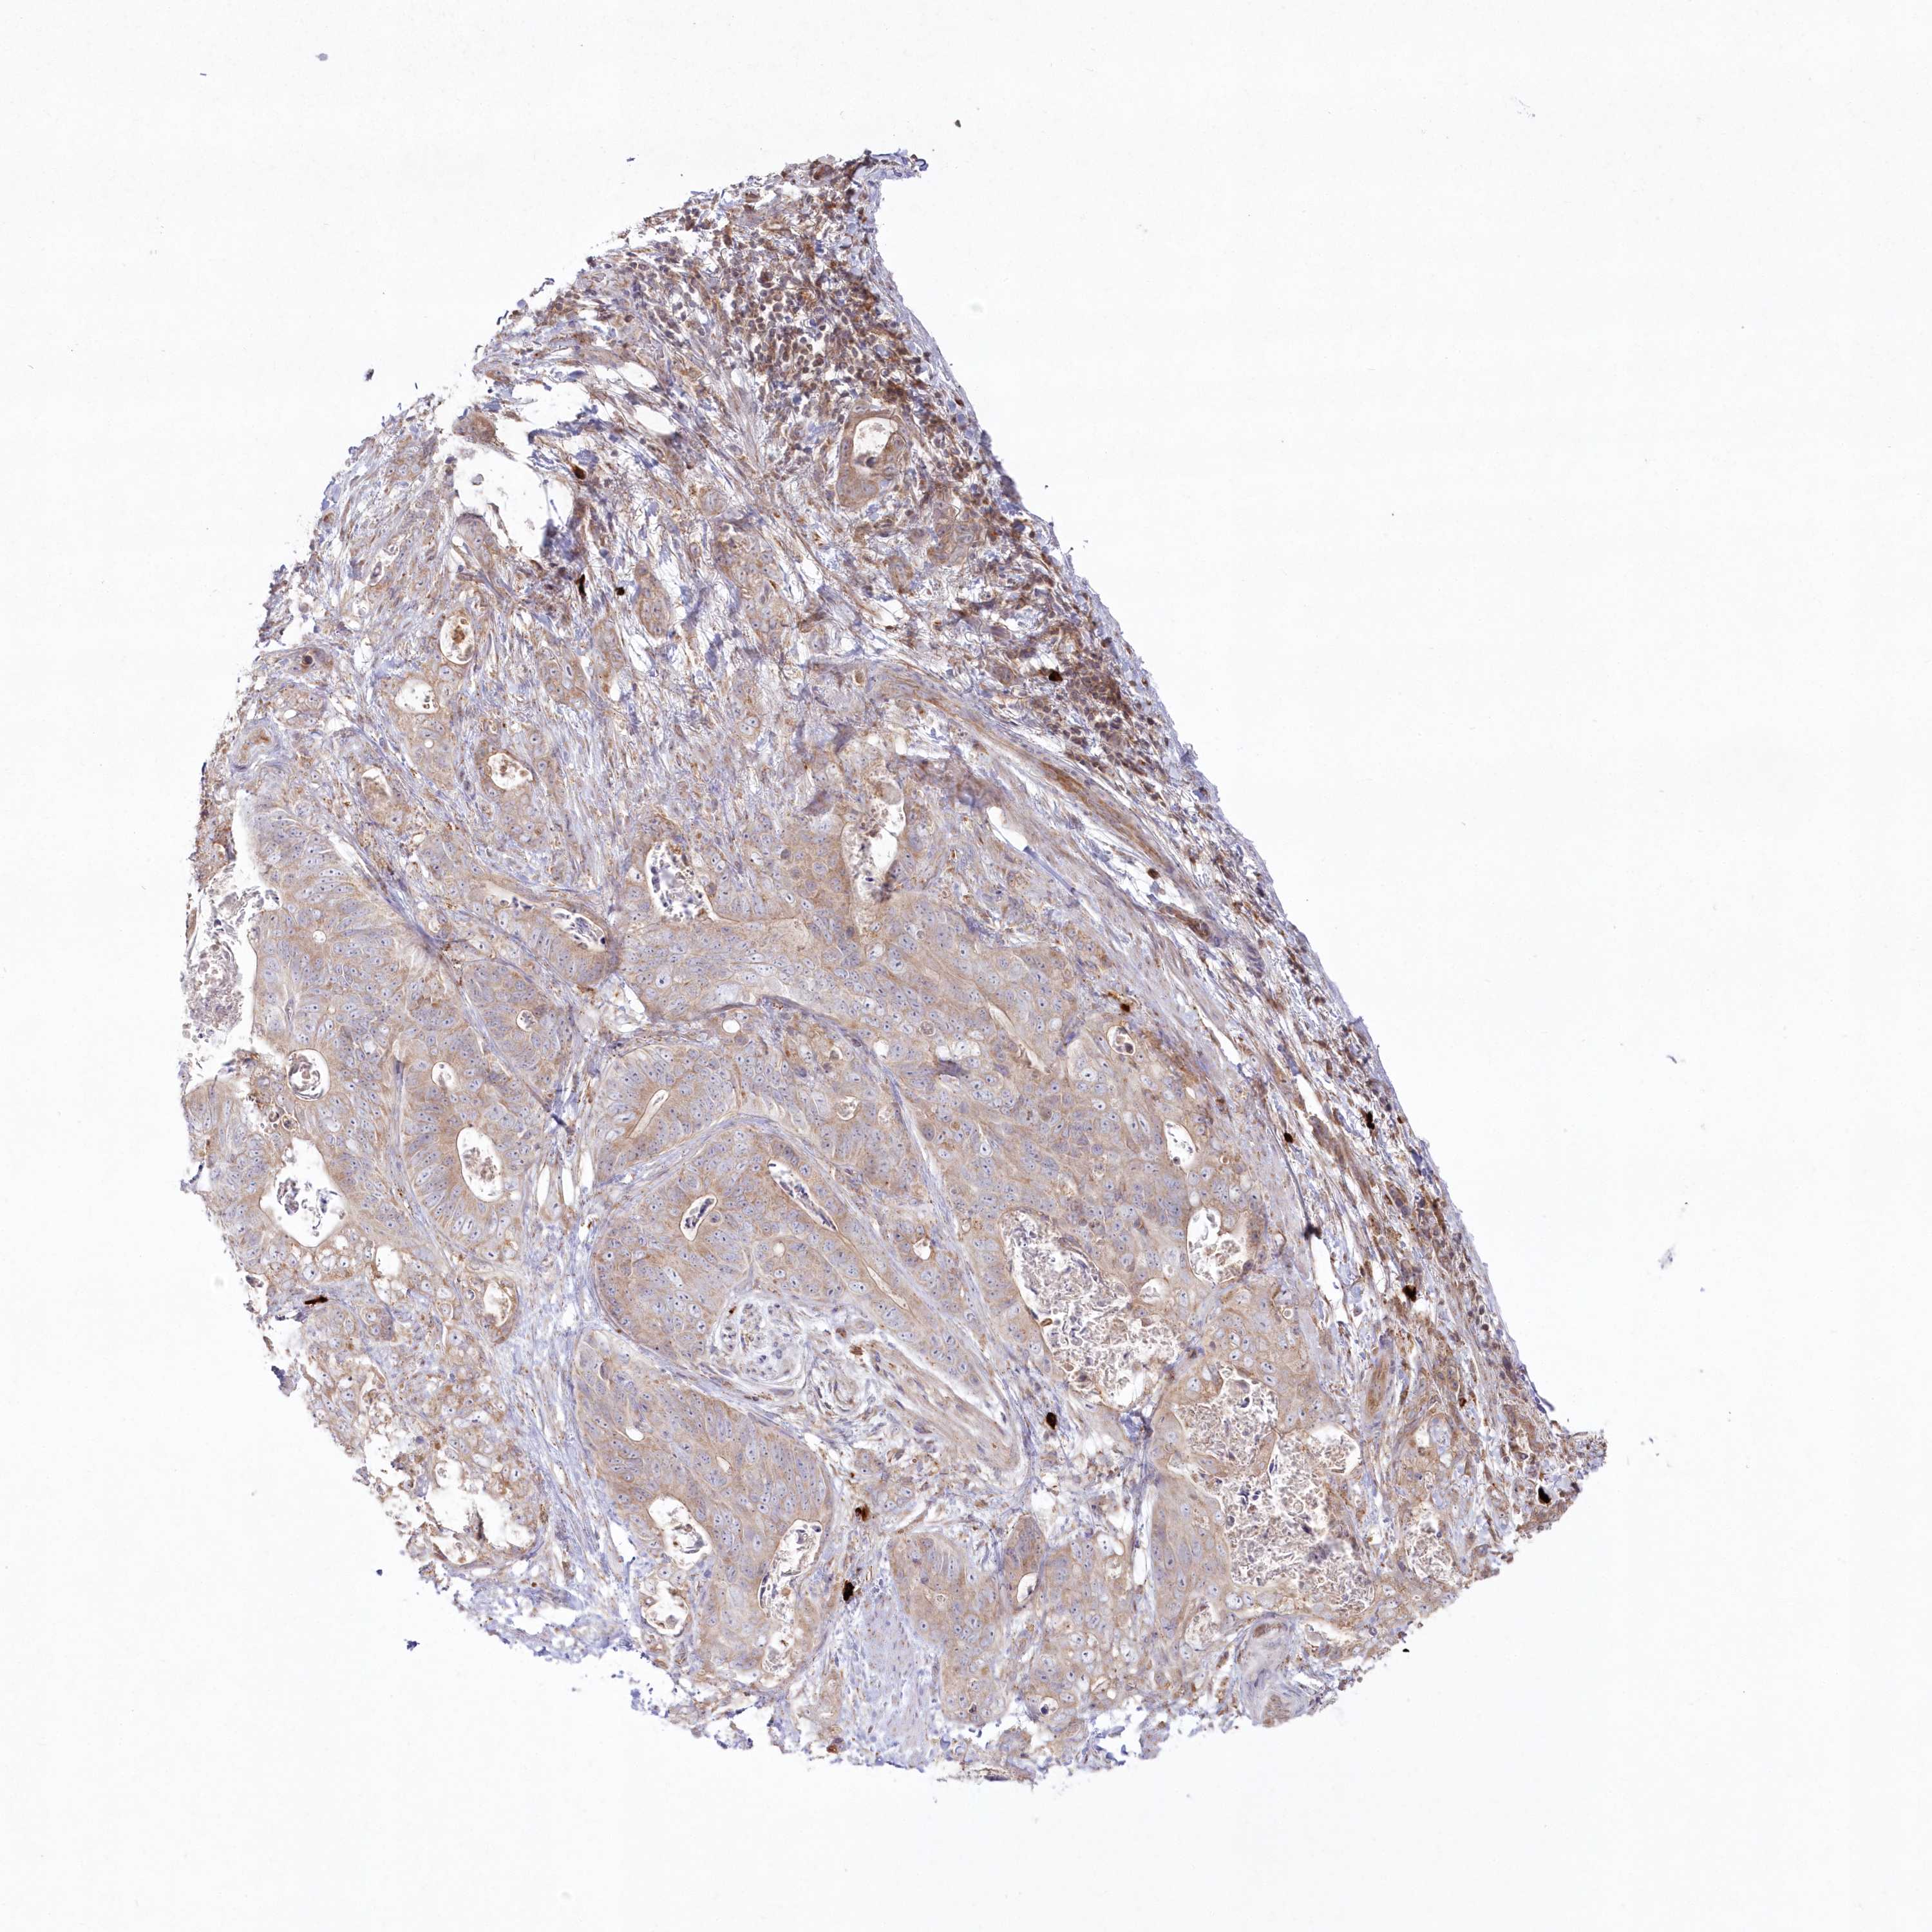

STOMACH CANCER - Protein expressioni

A mouse-over function shows sample information and annotation data. Click on an image to view it in a full screen mode. Samples can be filtered based on level of antibody staining by selecting one or several of the following categories: high, medium, low and not detected. The assay and annotation is described here.

Note that samples used for immunohistochemistry by the Human Protein Atlas do not correspond to samples in the TCGA dataset.

Antibody stainingi

Antibody staining in the annotated cell types in the current human tissue is reported as not detected, low, medium, or high, based on conventional immunohistochemistry profiling in selected tissues. This score is based on the combination of the staining intensity and fraction of stained cells.

Each image is clickable and will lead to virtual microscopy that enables deeper exploration of all samples and also displays staining intensity scores, fraction scores and subcellular localization as well as patient and tissue information for each sample.

Antibody HPA037770

Antibody HPA037771

Staining

High

Medium

Low

Not detected

Adenocarcinoma, NOS